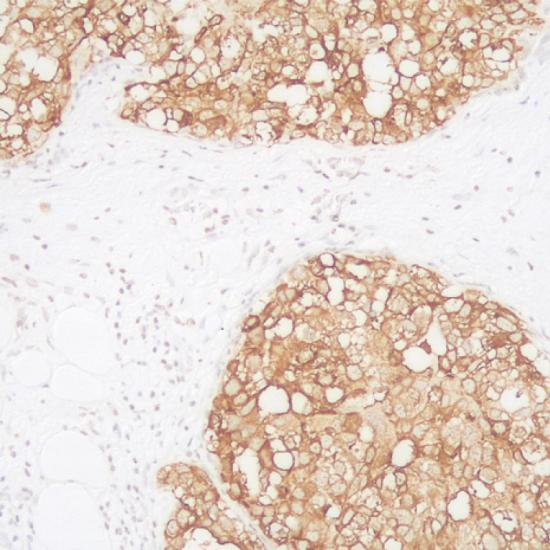

EMA抗體試劑(免疫組織化學(xué)) 閩廈械備20180055號(hào)

• 陽(yáng)性部位:

細(xì)胞漿/細(xì)胞膜

• 陽(yáng)性對(duì)照:

乳腺癌

EMA是一種400kDa糖蛋白,廣泛分布于各種上皮細(xì)胞及其來(lái)源的腫瘤。此抗體可以用于標(biāo)記上皮及上皮源性的腫瘤,EMA陽(yáng)性表達(dá)的腫瘤包括大多數(shù)的癌、間皮瘤、上皮樣肉瘤等,軟組織腫瘤一般呈陰性表達(dá)。